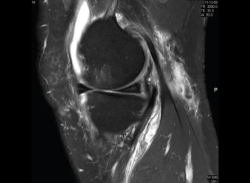

1.1. Meniscos

Figura 30. Corte de secuencia sagital T2 Fat-Sat de resonancia magnética de rodilla: menisco externo normal.

Se identifican como estructuras hipointensas en todas las secuencias, con asta anterior y posterior de morfología triangular.

Figura 31. Corte de secuencia sagital T2 Fat-Sat de resonancia magnética de rodilla: menisco interno normal.

La RM es la técnica de elección en el diagnóstico de la patología meniscal(17)(Figuras 30, 31, 32, 33, 34 y 35).